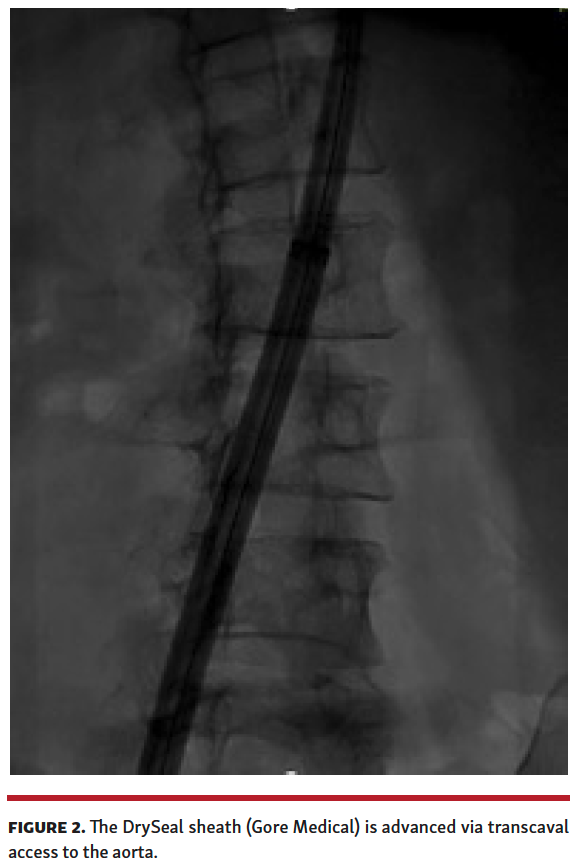

The patient’s iliofemoral and subclavian vessel size precluded percutaneous cannulation. We decided to perform transcaval aortic access to facilitate passage of a 26 Fr DrySeal cannula (Gore Medical).

Given the proximity of the thrombus to the left subclavian, bilateral cerebral embolic protection was performed with 2 Sentinel cerebral embolic protection devices (Boston Scientific) (Figure 1). We then obtained transcaval access using standard technique (Figure 2) and a 26 Fr DrySeal sheath was placed across the retroperitoneum into the abdominal aorta. A 17 Fr cannula (Edwards Lifesciences) was placed into the contralateral vein to serve as the AngioVac return cannula. A 180° Gen 3 AngioVac catheter was then prepped in standard fashion and advanced through the 26 Fr DrySeal sheath; it was then engaged with transesophageal echocardiography guidance in the aortic thrombus, and the mobile part was successfully aspirated (Figure 3 and Video 2) with small residual clot that was adherent to the aortic wall (Video 3). The patient was discharged on therapeutic warfarin.